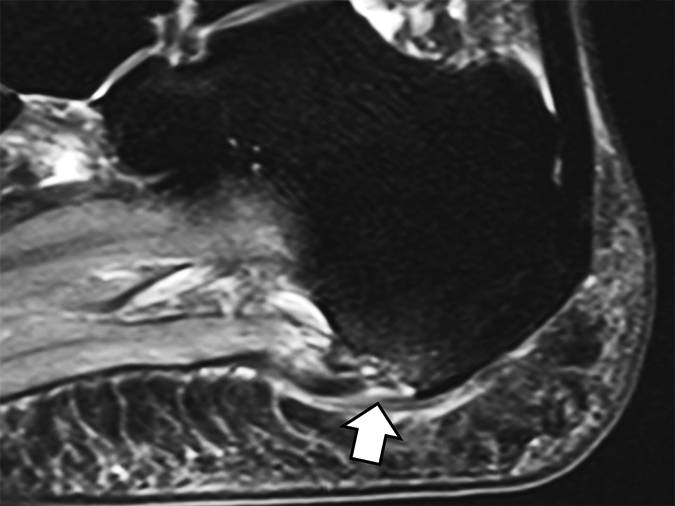

图11A -28岁男性曲棍球运动员扭伤。A,正位片显示侧向脚肿胀,其中心正好在第五跖骨的基部附近(直箭头)。 有小的线性骨块位于跟骰关节侧面(弯曲的箭头)。

图11B 轴向质子密度MR图像显示撕裂发生在骰骨附件的远端,表现为韧带和长骰骨之间的间隙(箭头)。韧带的近侧方面可以看到其跟骨附着。